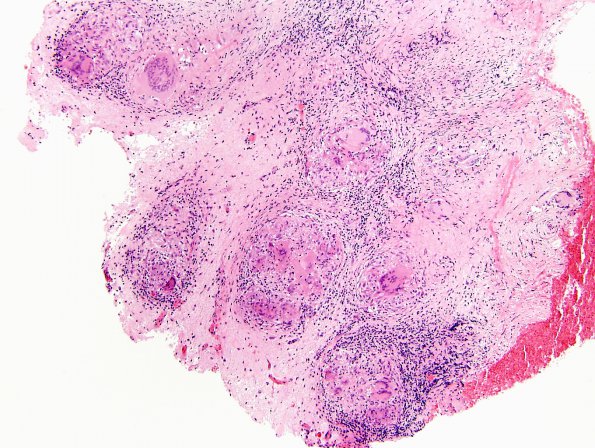

8B1-5 Granulomatous inflammation in connective tissue in the superficial temporal lobe shows prominent granulomas with epithelioid histiocytes and multinucleated giant cells (H&E)